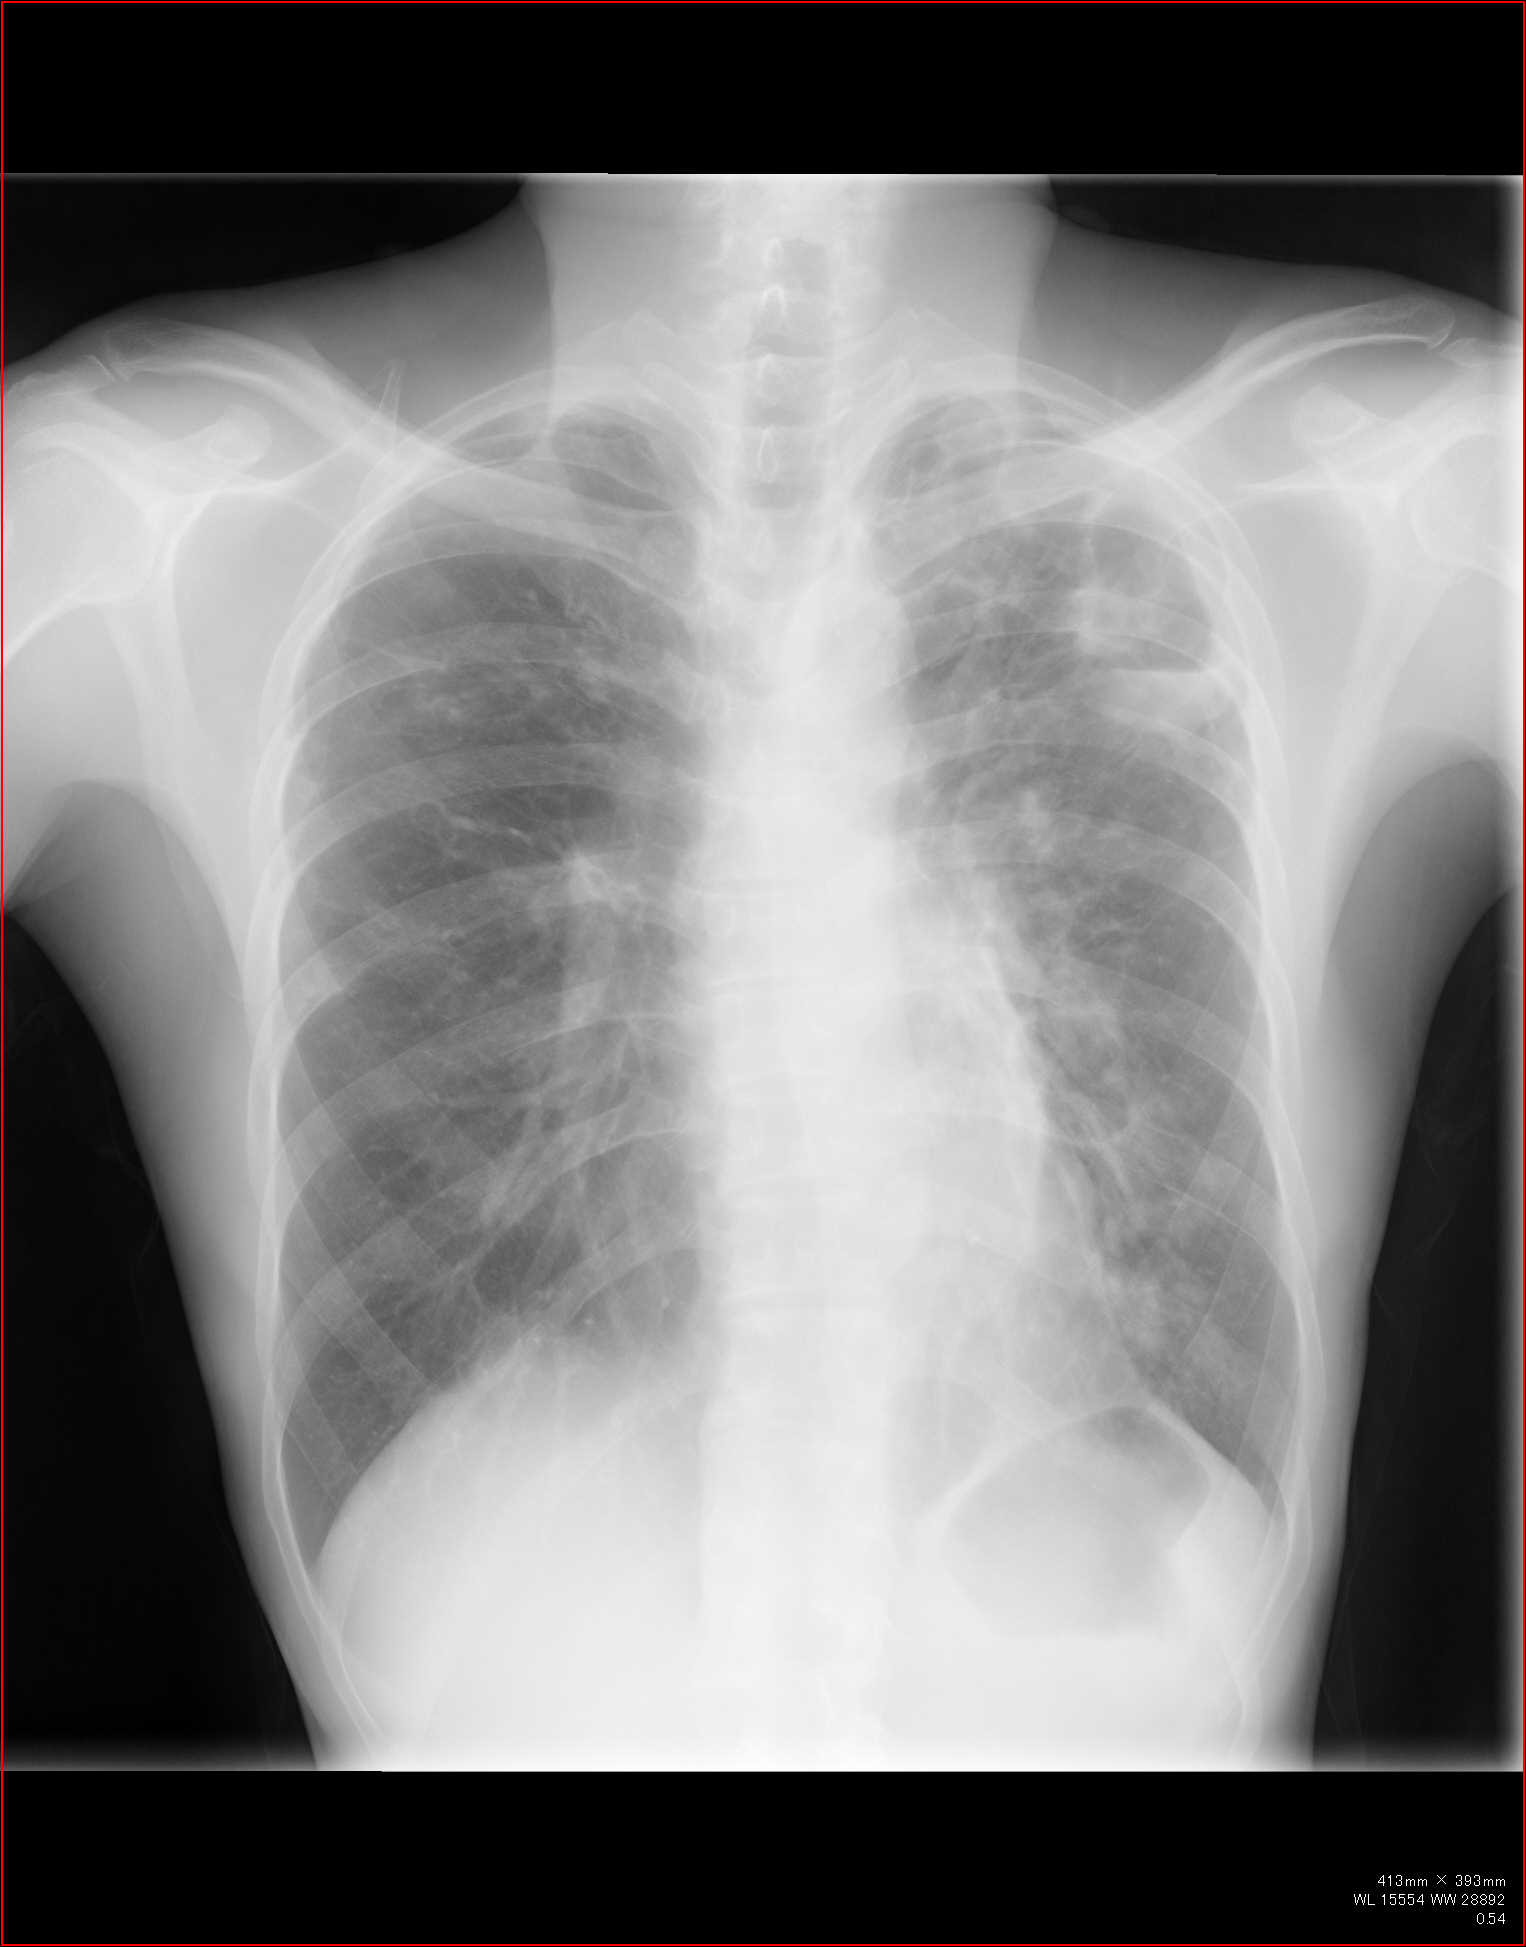

こちらを見て下さい。

わかりにくいかもしれませんが、このあたり。

気管が追いにくい、無くなっているようにも見えます。